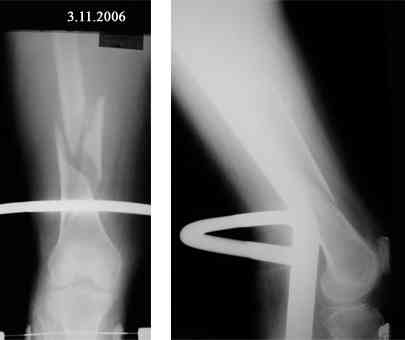

Представляю вашему вниманию снимки в динамике

Закрытый АВФ в этой ситуации может решить Ваши проблемы. Главное не размещать в проксимальном отделе бедра спицевую опору. Чаще всего именно там возникают воспалительные осложнения. Выход: либо "опустить" проксимальную опору к перелому, либо сделать ее стержневой. Срок фиксации правда 3 - 4 мес. На операции после восстановления оси отломок желательно "пришить" сквозной спицей с упором или консольной спицей.

После размещения рентгенограмы можно более конкретно обсудить схему фиксации.